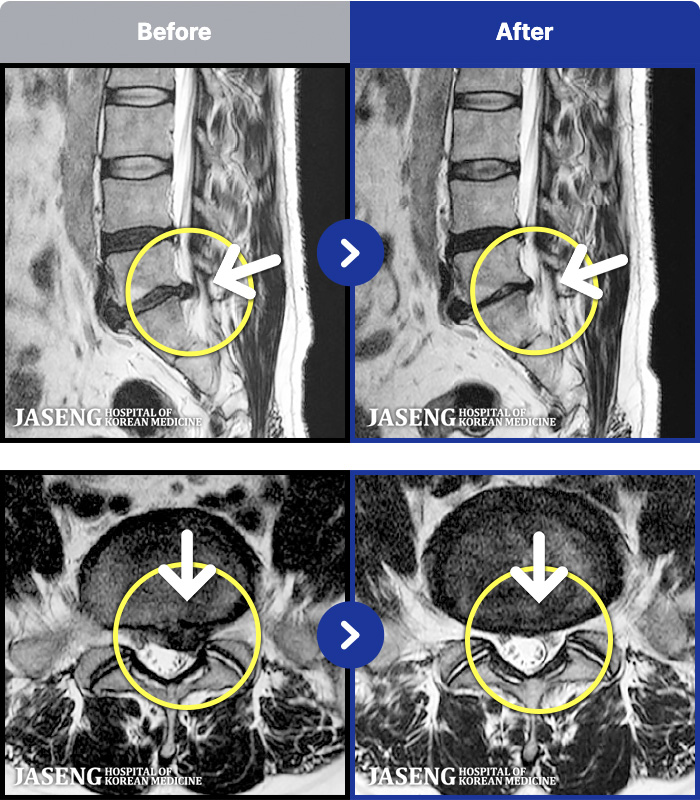

MRI ġ

1,237 MRI ũ ʸ Ȯϼ.